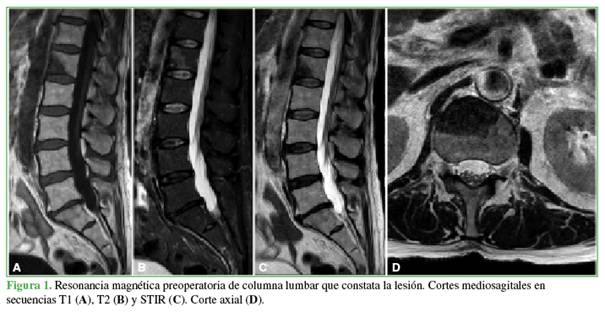

Imágenes preoperatorias

En la Figura 1, se muestran las imágenes de resonancia magnética de columna lumbar, con cortes sagitales, de las secuencias T1, T2 y STIR, así como un corte axial sobre el cuerpo vertebral de L1. Se observa una lesión que compromete la estructura del cuerpo vertebral e involucra la columna anterior en relación predominante con el segmento L1-L2, sin compromiso del canal vertebral, hipointensa en las secuencias T1/T2 e hiperintensa en la secuencia STIR.